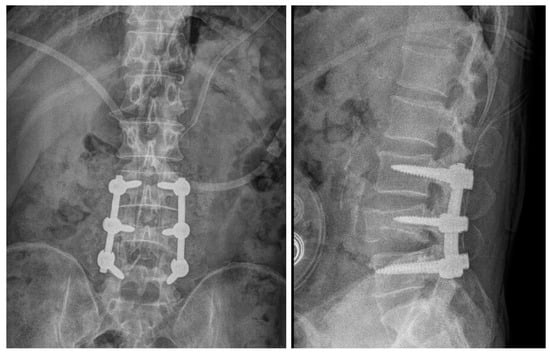

2.2. Case 2